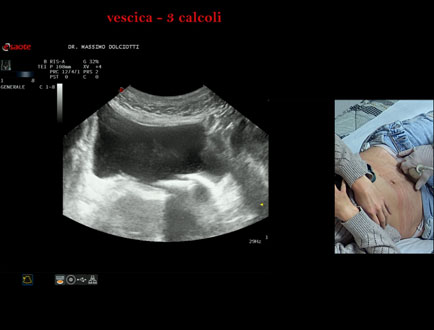

Data inserimento: 21/10/2025

Ecografia del: 15/10/2025

Strumento: Esaote MyLab Eight

Sonda: Convex Multifrequenza 1-8 MHz

Età Paziente: F 45 anni

Motivazione dell'esame: da alcuni mesi, disuria ed infezioni urinarie recidivanti.

Commento all'esame: le immagini ed il video documentano 3 immagini iperecogene, con cono d'ombra posteriore, da ricondurre a litiasi multipla della vescica.

Conclusioni: 3 calcoli della vescica (3 bladder stones).